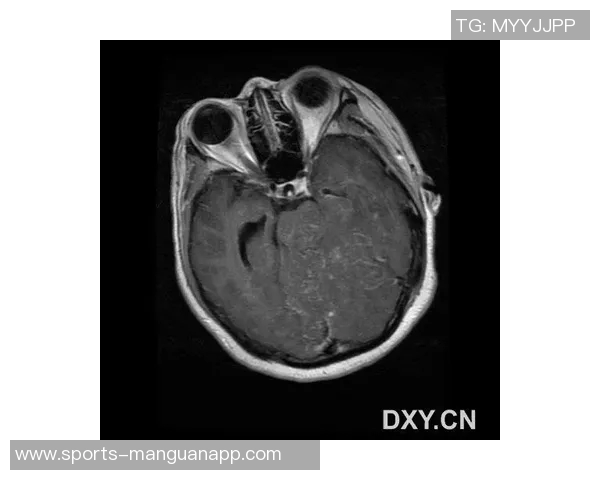

MRI(磁共振成像)是一种常见且有效的医学影像技术,广泛应用于运动医学领域。它能提供清晰、高分辨率的人体内部组织图像,使医生可以更准确地判断病变情况。在运动员受伤后,通过MRI检查,他们的骨骼、软组织和关节等部位都能够被详细扫描,从而帮助医生做出科学合理的诊断。

对于专业运动员来说,及时进行MRI检查至关重要。一方面,它能帮助快速确认损伤程度,从而制定相应的治疗方案;另一方面,也能为运动员提供心理上的安慰,让他们对恢复充满信心。当文班接受MRI检查时,他不仅是在寻求医疗建议,更是在与潜在恐惧抗争。